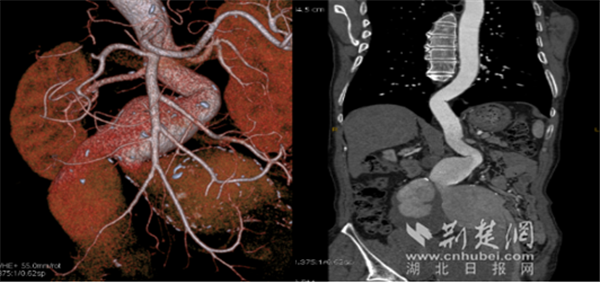

CTA检查提示腹主动脉、髂动脉多发巨大动脉瘤。通讯员供图

65岁陈先生,最近发现自己的腹部莫名其妙鼓包,而且还会规律性搏动。CTA检查提示,他患上了巨大腹主动脉瘤。感受到生命受到威胁,陈先生慕名找到武汉大学人民医院血管外科邓宏平教授团队。

入院后邓宏平教授向陈先生及患者家属详细地分析了病情:陈先生腹主动脉下段、双侧髂总动脉及双侧髂内动脉均有巨大动脉瘤合并血栓形成,最大瘤体直径达10cm,可能随时动脉瘤破裂大出血,或者是因粥样斑块、血栓脱落导致远端肢体栓塞。而且动脉瘤瘤体排成了一串“不定时炸弹”。既要完全消除瘤体,又要完整保护器官功能,手术难度指数级增加。